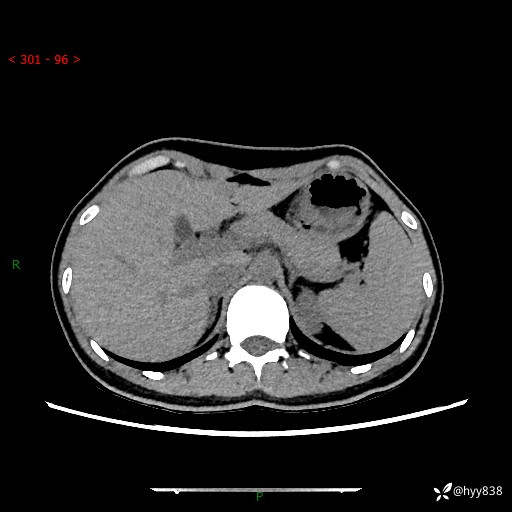

性别:女

年龄:23岁

简要病史:外院发现肝结节,来我院进一步增强确诊

上腹部CT平扫+增强